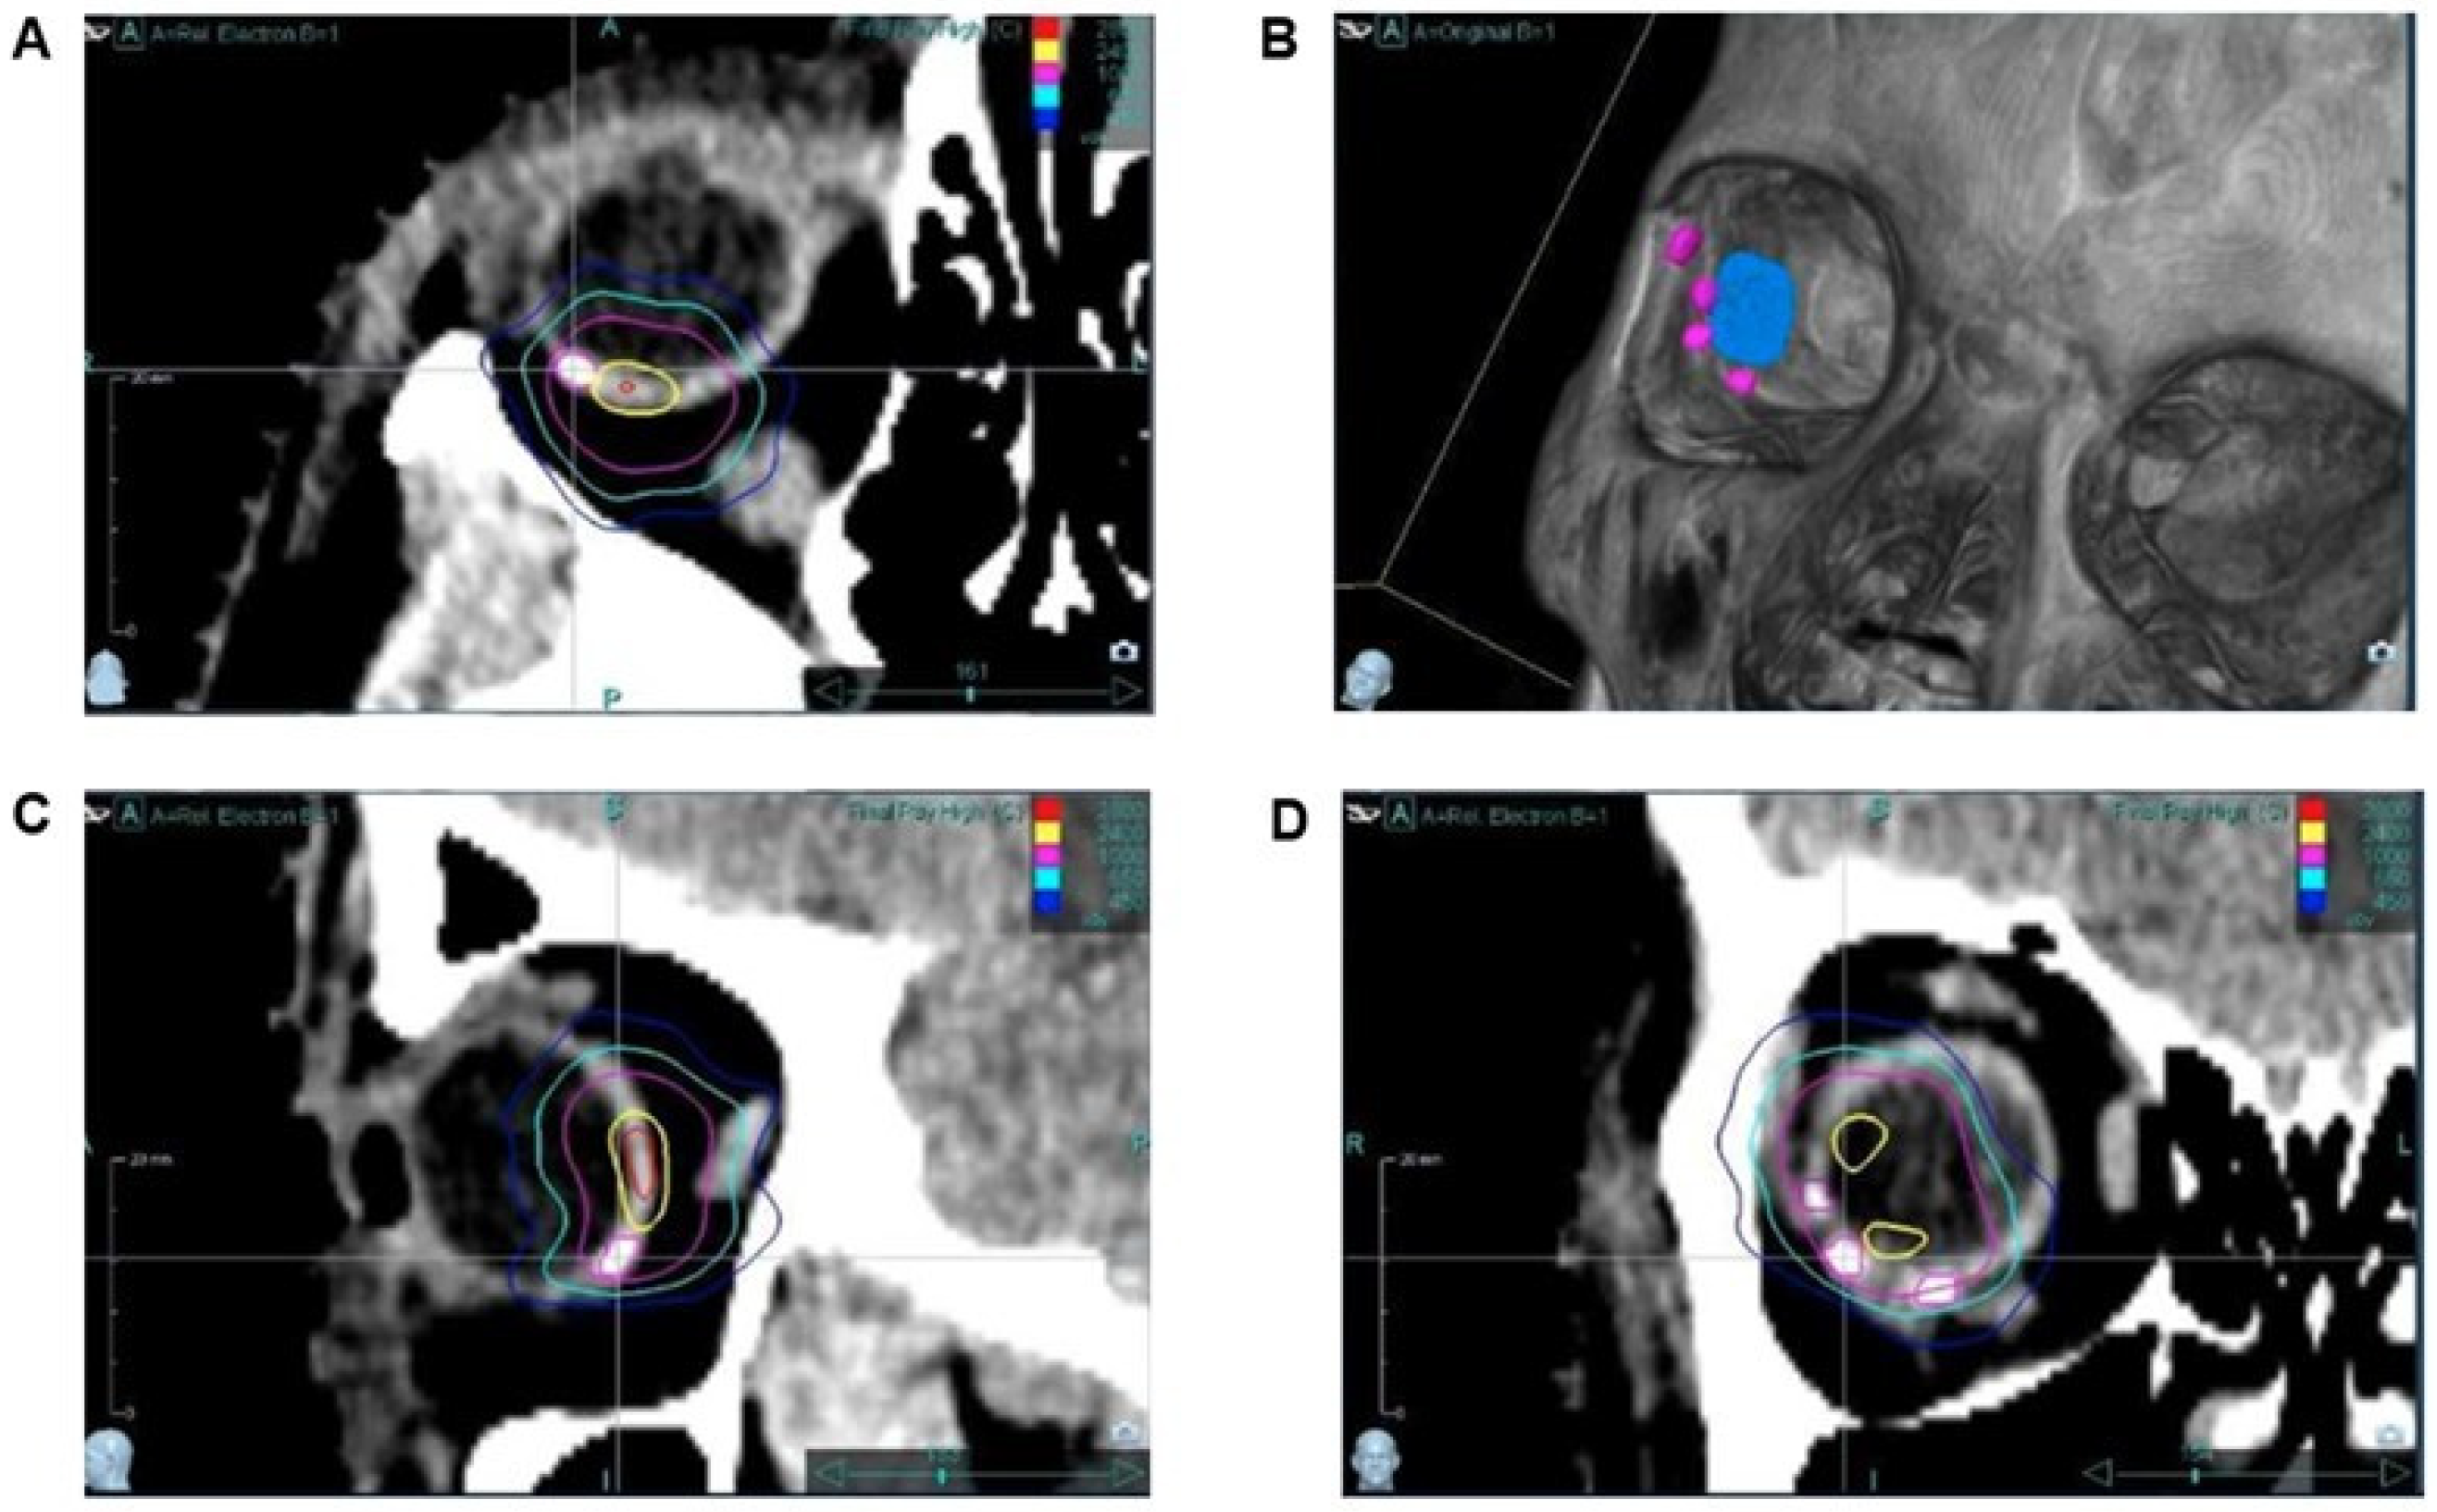

2.3. Treatment Planning

3.3. Stereotactic Radiosurgery